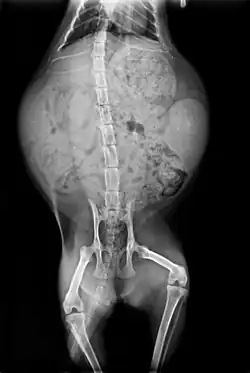

Radiographie d'une chatte gravide (à environ un mois et demi de gestation). L'image montre cinq fœtus de chatons, de tailles similaires.

La gestation dure 63 à 65 jours et une portée compte en moyenne quatre à cinq chatons, le maximum étant de huit[84]. Le ventre de la chatte commence à gonfler vers quatre semaines de gestation. À environ 35 jours, les mamelles de la femelle grossissent et rosissent. À sept semaines, elle commencera à chercher un endroit calme et convenable pour mettre bas (voir photographie ci-contre)[91].